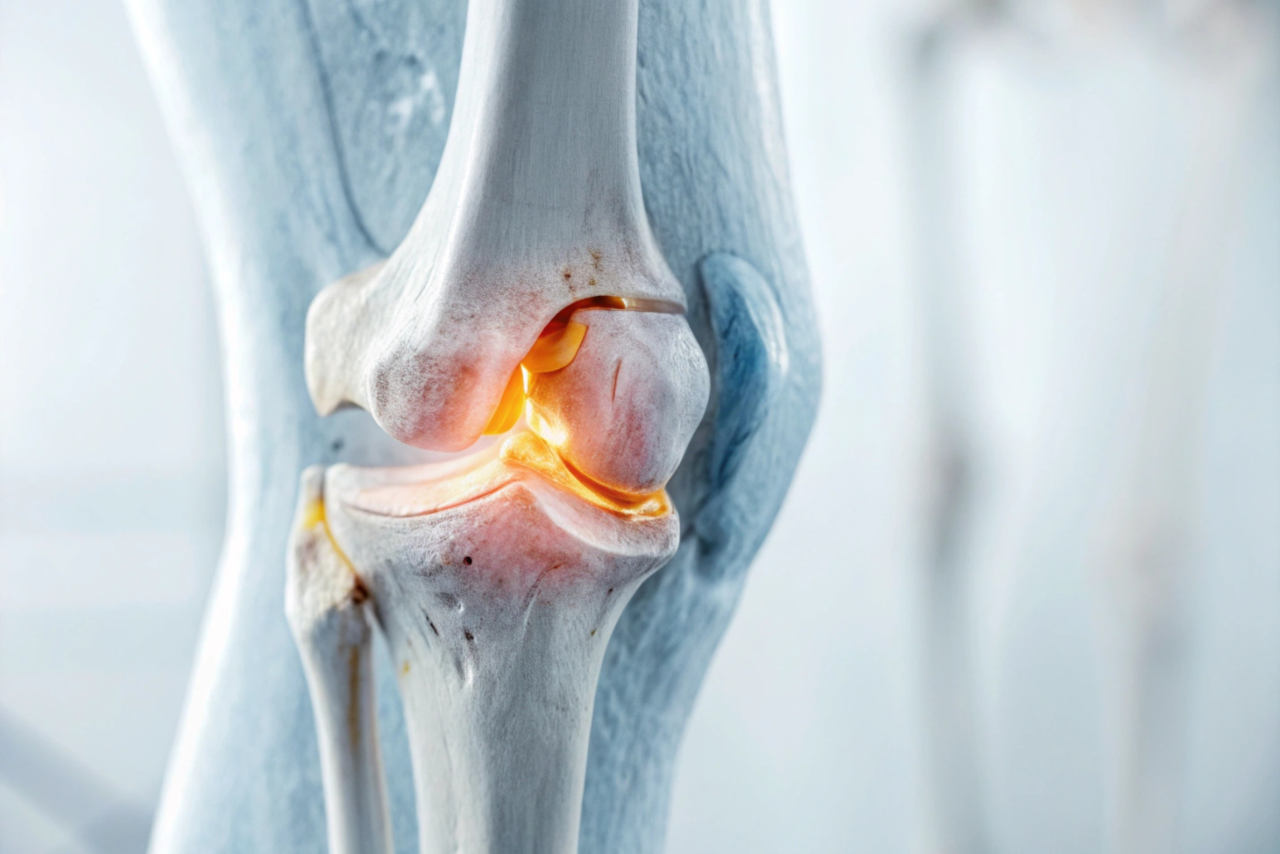

The Orthopedics Department at Health Point, led by the Best Orthopaedic Doctor in Ranchi, provides advanced evaluation, diagnosis, and treatment for disorders of bones, joints, muscles, tendons, and ligaments. Our orthopedic specialists focus on restoring mobility, relieving pain, and enabling patients to return to active and healthy lives. From sports injuries and fractures to joint replacement and spinal conditions, our team brings expertise supported by modern medical technology, precision-based surgeries, and personalized rehabilitation plans.

Whether it’s a child with a fracture, an adult with chronic joint pain, or a senior dealing with arthritis, as the Best Orthopedic Hospital in Ranchi, we deliver tailored treatment suited to every age. With state-of-the-art modular operation theatres, advanced physiotherapy and rehabilitation support, and the most modern arthroscopy and trauma surgery techniques, we ensure faster recovery and long-term results. Our approach goes beyond just treatment — we support lifestyle modification, post-surgical care, injury prevention, and long-term wellness for every patient.

- Shoulder, knee, and hip pain